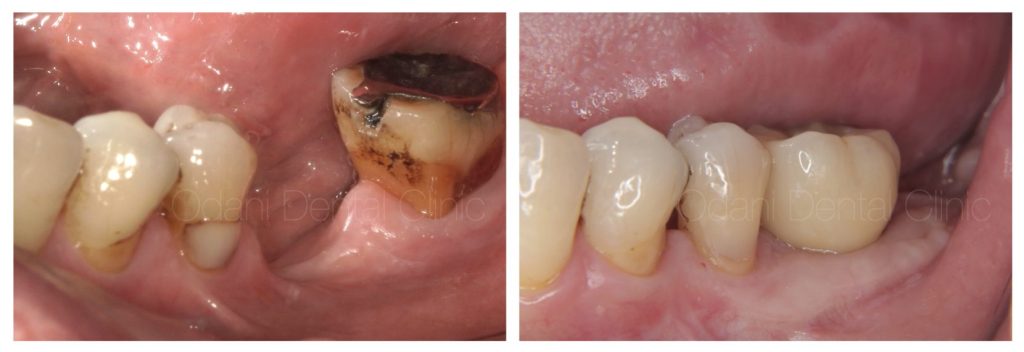

治療前と治療後の比較

最終的に予後不良の一番奥の歯は抜歯し、結果としてインプラントがより清掃しやすい環境となりました。

歯と歯ぐきと骨の連続性が得られ、すべてが管理しやすい状態となりました。